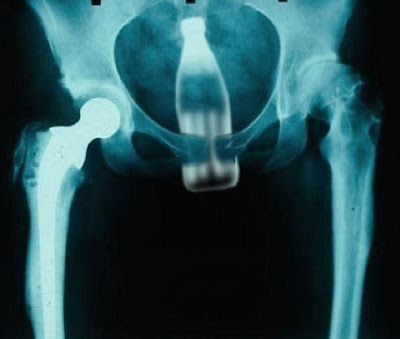

The Pepsi ChallengeThe man, who was 60 years old, reportedly required removal of the Pepsi bottle after armed thieves assaulted him with it before robbing him of his two buffalos.